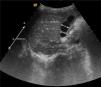

Se describe el caso de un niño de 2 años, sin antecedentes de interés, que consulta por vómitos, fiebre y deposiciones diarreicas de 3 días de evolución. Al ingreso presenta un estado de hidratación conservado, afebril, irritabilidad ante la manipulación, auscultación cardiorrespiratoria normal. El abdomen se muestra distendido, blando, depresible y sin megalias, con peristalsis aumentada. A nivel del cuadrante superior derecho del abdomen se palpa una masa dolorosa de consistencia blanda, bien delimitada y tamaño aproximado de 5cm de diámetro. En la analítica de ingreso destaca ligera elevación de la aspartato aminotransferasa: 68 U/l y de la proteína C reactiva: 12mg/l. La detección del antígeno de rotavirus en heces fue positiva. La ecografía abdominal muestra una vesícula biliar distendida con contenido espeso en su interior, sin dilatación de la vía biliar (fig. 1). Se instaura perfusión glucosalina, dieta absoluta y analgesia. A partir del tercer día del ingreso, se aprecia una mejoría clínica significativa con leve molestia a la palpación a nivel subcostal derecho; en la ecografía abdominal de control, se evidencia una disminución significativa del volumen de la vesícula biliar (fig. 2). El paciente recibe el alta hospitalaria y al mes se realiza un control ambulatorio, permaneciendo asintomático y con ecografía abdominal normal.

Debemos tomar en consideración que el hidrops vesicular de nuestro paciente se encontró asociado a una entidad sistémica, a la infección por rotavirus, sin dejar de mencionar que existen otros factores que pueden contribuir a este aumento del tamaño vesicular, como es el ayuno prolongado y la deshidratación. Habitualmente la resolución es espontánea, con recuperación del tamaño y la forma de la vesícula biliar.

Dada la naturaleza autolimitada de esta entidad, el tratamiento inicial debe ser conservador (tratamiento de la enfermedad asociada, corrección de las alteraciones subyacentes, iniciar alimentación precoz). La resolución es espontánea, con retorno de la función de la vesícula biliar a la normalidad en pocas semanas, tan solo en casos excepcionales la colecistectomía estaría indicada cuando se producen complicaciones como vesícula biliar gangrenosa, perforación o deterioro del estado clínico.